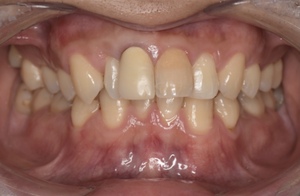

Before

After

基本情報

| 主訴 | 見た目をきれいにしたい |

| 治療期間 | 6ヶ月 |

| 治療費 | ジルコニアボンド(セラミックの被せもの)¥165,000×7(税込み) オフィスホワイトニング4回 ¥4,400×4(税込み) ホームホワイトニング¥11,000 |

| リスク・副作用 | かみ合わせがとても強い方の場合、稀に割れてしまうことがあります。 |

| 先生からの提案 | 上の前歯6本と右下の2番目の歯はセラミックの被せもので治療。 残りの下の前歯5本はプラスチックの材料で虫歯を治療し、 ホワイトニングをおこないました。白くなったご自身の歯の色に合わせてセラミックの 被せものを作成しています。 模型上で完成後をシュミレーションし、上の歯茎の位置をきれいに見えるように 揃えています。(外科処置はしていません) |